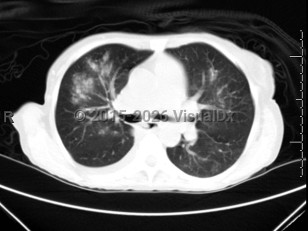

Fever, Cough, 50-59 year old Female

COVID-19